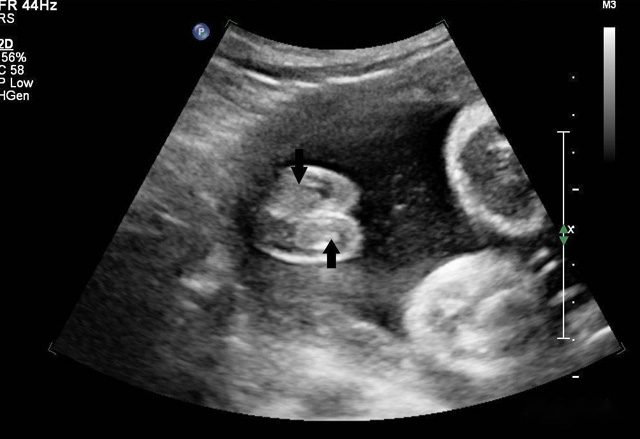

動(dòng)態(tài)三維超聲成像有時(shí)間因素(心動(dòng)周期)三維超聲成像分為靜態(tài)三維超聲成像和動(dòng)態(tài)三維超聲成像,整體成像法重建感區(qū)域?qū)崟r(shí)活動(dòng)的三維圖像,稱(chēng)為四維超聲心動(dòng)。

三維超聲技術(shù)可用于心臟、腹腔、婦科、產(chǎn)科、小器官、血栓、血管成像等多方面。